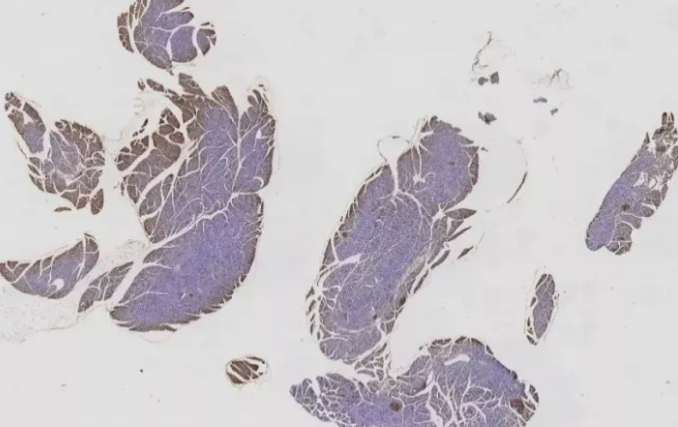

一、固定不充分

10%中性福爾馬林是目前應(yīng)用最廣泛且效果較好的固定方式。組織塊太大,或固定時(shí)間太短,都會(huì)導(dǎo)致固定不充分。一般8-24h為宜,具體還需要經(jīng)過實(shí)際操作摸索確定。如圖1的這種情況,可適當(dāng)延長固定時(shí)間到48h。

圖1 固定不充分